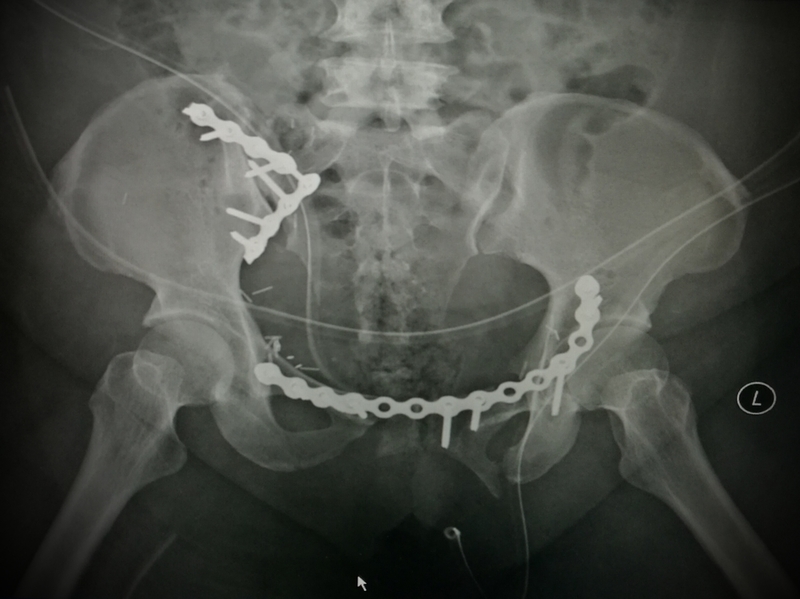

Addressing at a workshop on “ pelvi Acetabular and Complex hip replacement ‘ held at an Annual Anthroplasty Conference being organized by the Telangana Othopaedic Surgeon’s Association (TOSA) along with Twin Cities Orthopaedic Society (TCOS) here, Dr Myneni, who is also the conference Secretary of the conference, said “Pelvis and hip bones protects vital organs like urinary bladder, genitals, blood vessels supplying lower limbs. People may die within few minutes to few hours if these fractures are not diagnosed early and treated accordingly in emergency specialised centres.'

While driving, people should be more vigilant in wearing seat belts, avoid drunken driving and late night driving on high ways. Avoid over speeding since prevention is better than cure, said Dr Myneni, who is also the Conference Organizing Secretary, added. Renowned Orthopaedic Surgeon Dr Ramesh Sen from Chandigarh besides eminent national and local Orthopaedic faculties from across the places like Mumbai, Chennai, Coimbatore, were among the participants. This conference focused on the management of patients with fractures of Pelvis and Acetabulum and faculty of experts shared an integrated multidisciplinary approach to comprehensive treatment at the event.

Surgical approaches too were video demonstrated by the experts. In addition to lectures and workshops, interactive sessions with the discussion of clinical scenarios, their optimal management along with case presentations was also done.